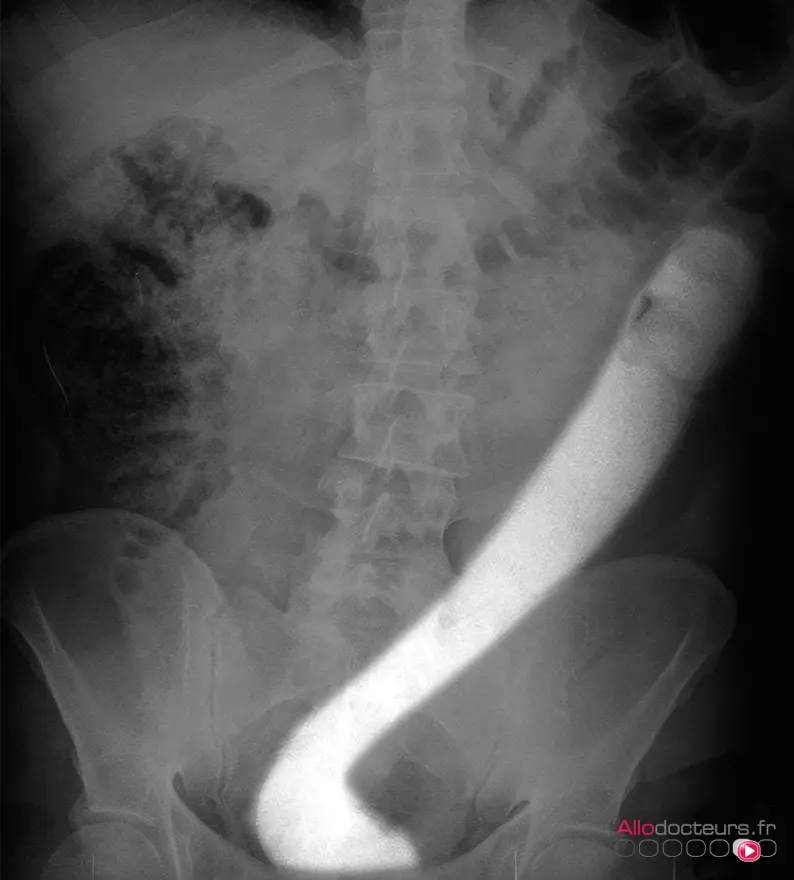

Mais dans le cœur de l’un des membres de l’équipe vibrait l’âme d’un MacGyver. Celui-ci a assemblé "un dispositif « maison » (sic), en insérant un fil dans un cathéter […] afin de créer un nœud coulant". L’idée était d’enserrer le sextoy dans ce lasso, puis de le guider avec douceur vers la sortie.

La première tentative fut une réussite. "Cette nouvelle technique [nous apparaît] une option valable pour extraire les gros corps étrangers du côlon et du rectum, lorsque les méthodes endoscopiques standard échouent", écrivent les membres de l’équipe dans leur article.

L'invention des urgentistes italiens, telle que présentée dans leur article.